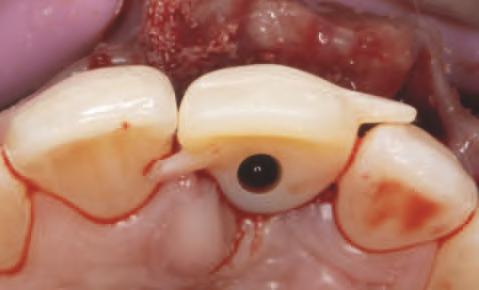

Implantur le subper ostale sunt structur metal ce fabr cate nd vdual pentru a se adapta ș a restab l zonele edentate. Personal zate ș concepute pentru a se potr v morfolog e osoase un ce a pac entulu , mplantur le subper ostale sunt plasate sub per ost ș sunt stab l zate pr n șurubur de f xare care ntră în contact cu osul sub acent ș țesutul f bros care le acoperă. Spre deoseb re de mplantur le convenț onale, mplantur le subper ostale se sprj nă d rect pe os ș prez ntă bontur care emerg pr n țesutur le g ng vale pentru a acomoda proteze f xe sau detașab le totale sau parț ale (un exemplu de implant subperiostal individualizat este ilustrat în fig. 6-14)

În z ua nserăr , după ce s-a real zat o expunere suf c entă a suportur lor anatom ce sub acente, mplantul este ver f cat în pr v nța adaptăr corecte, ar or ce mod f căr necesare sunt efectuate îna nte de plasarea f nală. Implantul este stab l zat pe poz ț e cu șurubur monocort cale nserate pr n găur predef n te în osul sub acent. Lamboul este decolat ș d secat corespunzător pentru a obț ne suf c entă pas v tate care să as gure o înch dere pr n ntenț e prmară în jurul bontur lor expuse ale mplantur lor. După per oada necesară de v ndecare, se au amprentele corespunzătoare pentru fabr carea ș l vrarea proteze f nale.

Progresele recente în tehnolog a CBCT ș prec z a mag n lor au redus t mpul de tratament la o s ngură ses une ch rurg cală, deoarece schelet zarea max larulu rez dual al pacentulu nu ma este necesară pentru fabr carea proteze . Pr ntarea 3D ș , în spec al, tehnolog a DMLS perm t de asemenea fabr carea personalzată a scheletulu subper ostal cu mplantur , perfect adaptat anatom e spec f ce a pac entulu . Aceste cal tăț au st mulat nteresul pentru ut l zarea mplantur lor subperostale, în spec al pentru gest onarea pac enț lor cu atrof complexe ș stor c de traumat sme ș /sau ablaț e/rezecț e tumorală, unde opț un le de mplantur fără grefe pot să nu f e fezab le. În or ce caz, ntervenț a ch rurg cală pentru plasarea unu mplant subper ostal este tehn c ma complexă decât poz ț onarea clas că a mplantur lor ntraosoase. Pr n urmare, ab l tatea ch rurg cală